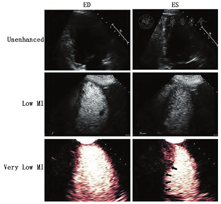

视觉定性分析更容易学习和减少劳动强度(图7和图8,视频10;可从www.onlinejase.com获得)。以下经验法则可用于结果判读:使用2D超声探头进行静息再充填应该在高机械指数脉冲闪击破坏后5 s内,在负荷状态下应2 s内再充填(视频6和7;在www.onlinejase.com获取)[1]。

在任何形式的负荷成像过程中,二维成像平面的再充填应该是一致的,并且静息状态在5 s内、负荷状态下在2 s内再充填。图11显示了高机械指数脉冲后正常的静息状态和负荷后的再充盈情况。图12和图13是在多巴酚丁胺负荷期间不同冠状动脉区域中诱导的心肌灌注缺损的示例。